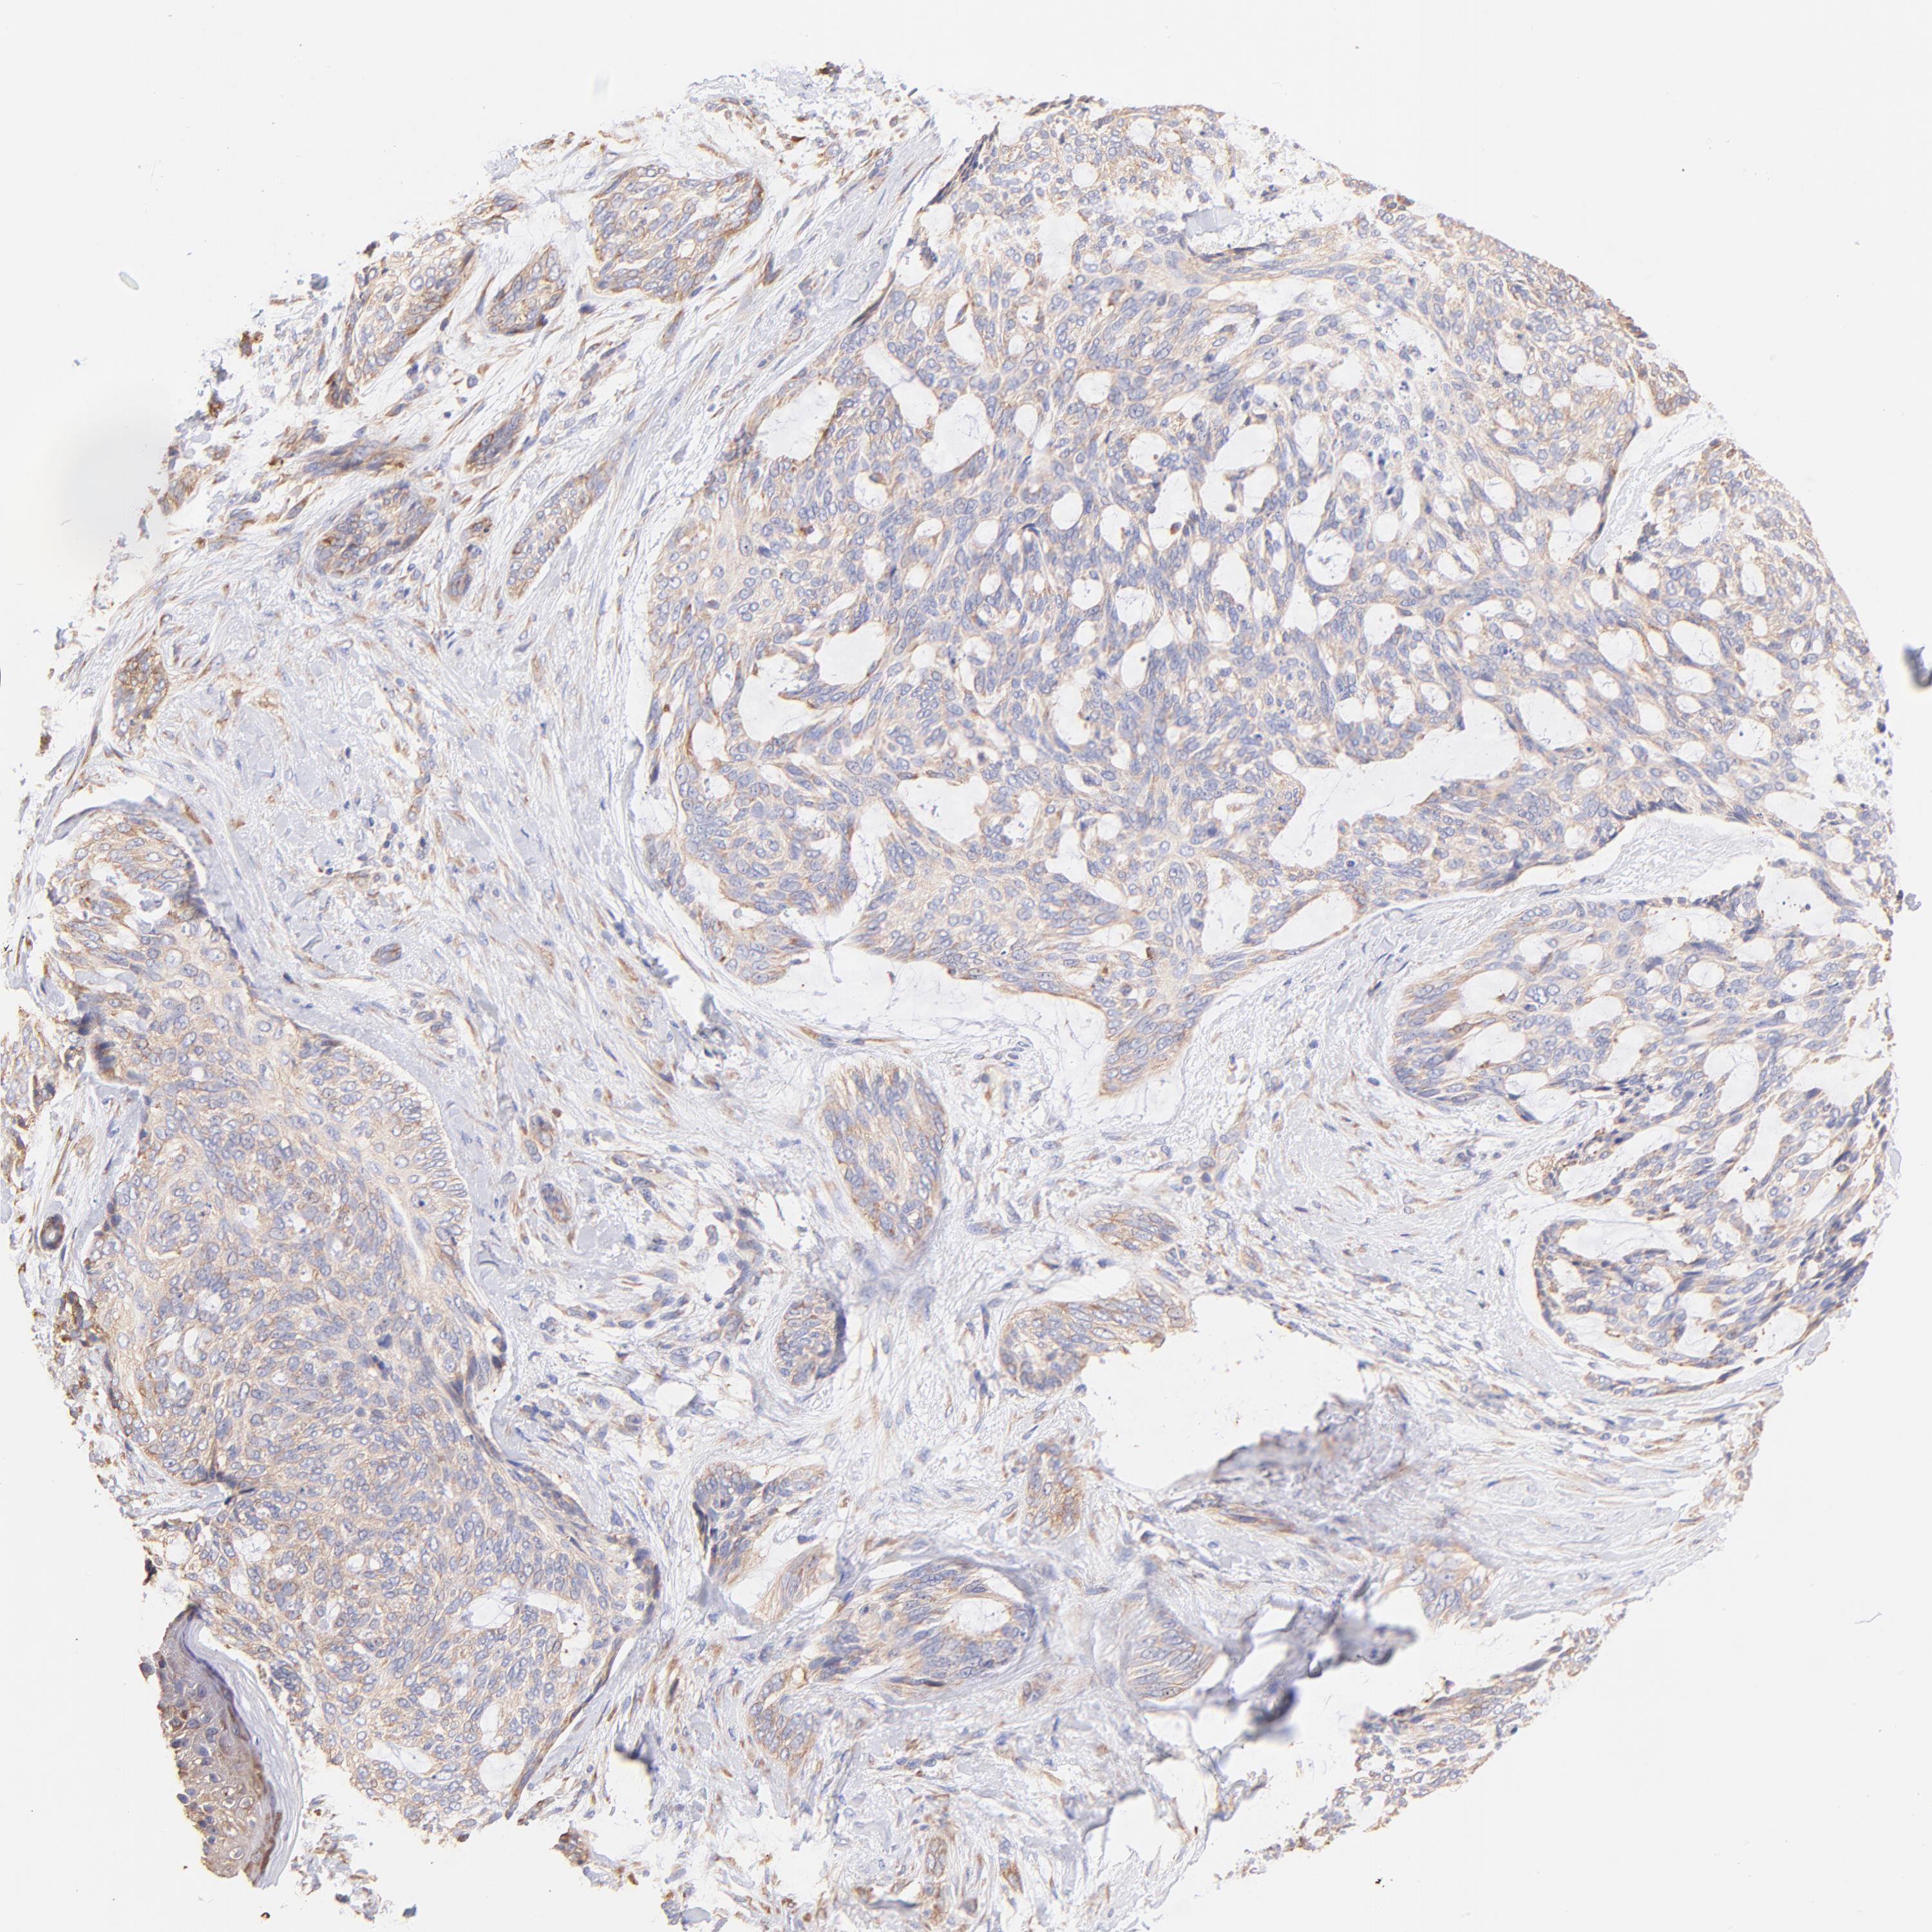

SKIN CANCER - Protein expressioni

A mouse-over function shows sample information and annotation data. Click on an image to view it in a full screen mode. Samples can be filtered based on level of antibody staining by selecting one or several of the following categories: high, medium, low and not detected. The assay and annotation is described here.

Antibody stainingi

Antibody staining in the annotated cell types in the current human tissue is reported as not detected, low, medium, or high, based on conventional immunohistochemistry profiling in selected tissues. This score is based on the combination of the staining intensity and fraction of stained cells.

Each image is clickable and will lead to virtual microscopy that enables deeper exploration of all samples and also displays staining intensity scores, fraction scores and subcellular localization as well as patient and tissue information for each sample.

Antibody HPA002651

Staining

High

Medium

Low

Not detected

Intensity

Strong

Moderate

Weak

Negative

Quantity

>75%

75%-25%

<25%

None

Location

Nuclear

Cytoplasmic/membranous

Cytoplasmic/membranous,nuclear

Squamous cell carcinoma, NOS

Basal cell carcinoma